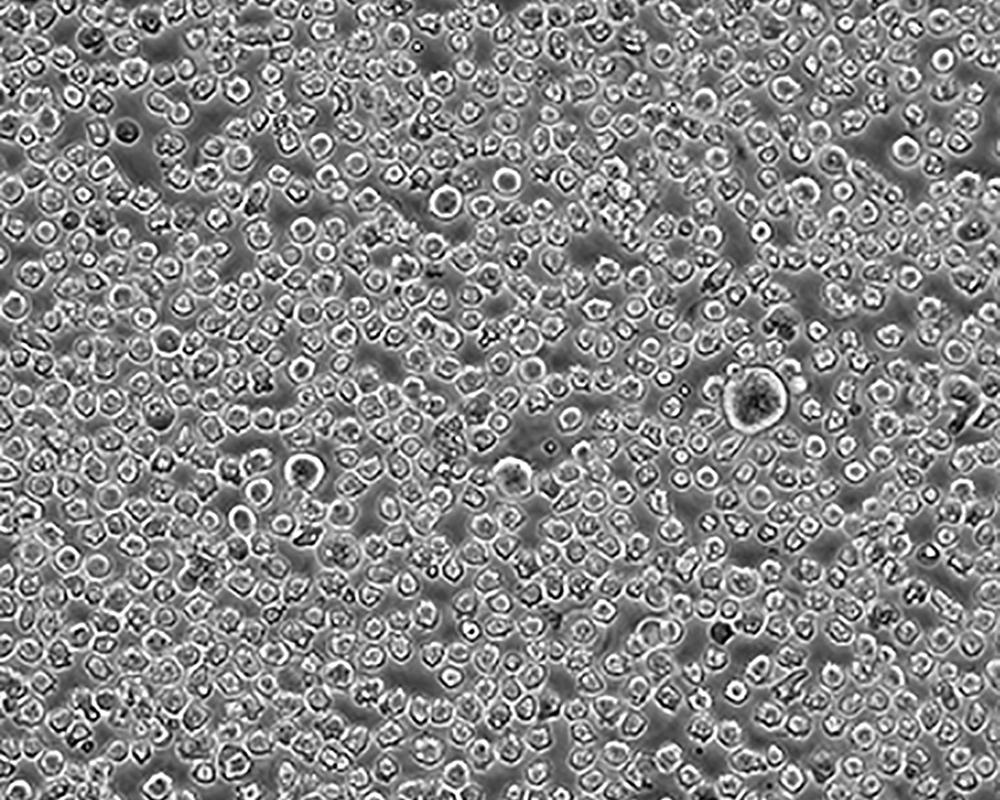

生長特性 suspension

形態(tài)特征 lymphoblast

細(xì)胞描述 The cell population has been characterized as highly undifferentiated and of the granulocytic series. Studies conducted by Anderson, et al. , on the surface membrane properties led to the conclusion that the K-562 was a human erythroleukemia line. K-562 blasts are multipotential, hematopoietic malignant cells that spontaneously differentiate into recognizable progenitors of the erythrocytic, granulocytic and monocytic series. The effect of inducers on sublines derived from the original K-562 cell line have been reviewed by Koeffler and Golde. Karyological studies on various K- 562 sublines have been classified into three groups(A,B,C) by Dimery, et al. The strain obtained by the ATCC most closely resembles the B population. Occurrence of the Philadelphia chromosome, however, was of much lower frequency; none detected in 15 metaphases examined. The line is EBNA negative.